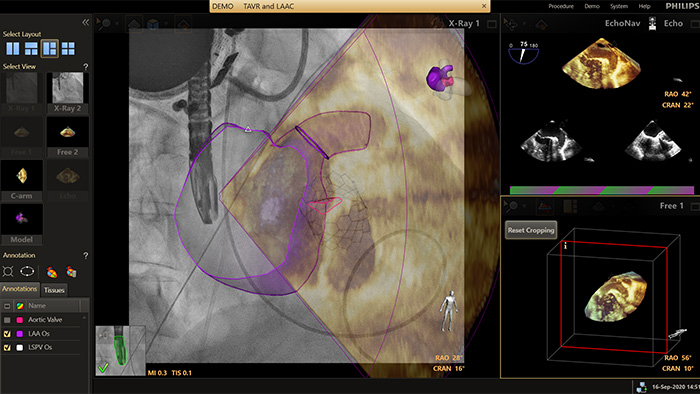

EchoNavigator

EchoNavigator reorients and combines ultrasound and X-ray information into a single augmented visualisation for guidance and device-tissue relationship assessment. In LAA occlusion EchoNavigator enables the following to elevate confidence and boost efficiency:

HeartNavigator

The HeartNavigator is a CT planning and live overlay guidance solution using automatic heart model segmentation of anatomy to improve ease of use, speed and reproducibility. In LAA occlusion, HeartNavigator enables: